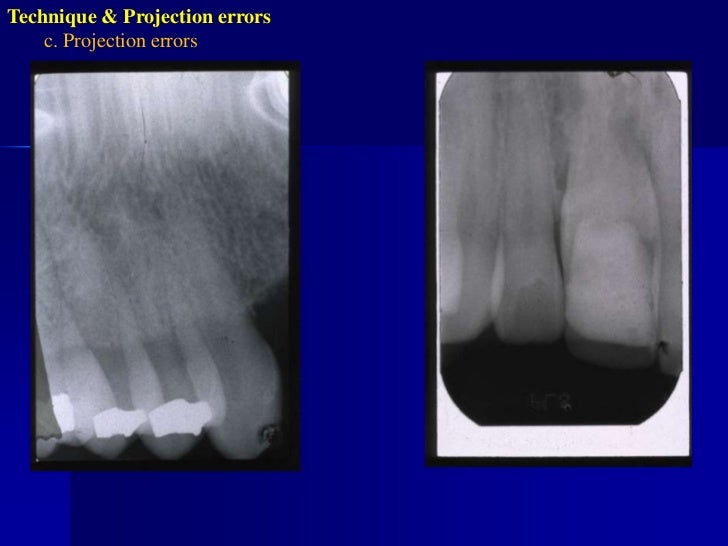

Errors of dental radiography